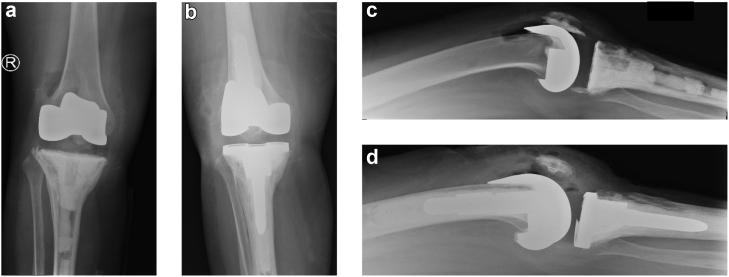

A 51-year-old woman suffered cardiac arrest requiring emergent intraosseous access that abutted the tibial component of her total knee arthroplasty. She developed a wound at the site and knee pain which was concerning for deep infection. Subsequent imaging was consistent with osteonecrosis developing around the tibial component. The component eventually loosened, requiring a revision surgery. Her deep cultures remained negative throughout. Her findings are most consistent with osteonecrosis and aseptic loosening of her prosthesis. While intraosseous access may be beneficial during resuscitation, it has complications. This is the first reported case of osteonecrosis secondary to intraosseous access leading to prosthetic loosening necessitating a revision surgery.

一名51岁女性发生心脏骤停,需要紧急进行骨内通路穿刺,穿刺部位紧邻其全膝关节置换术的胫骨部件。她在该部位出现了伤口和膝关节疼痛,令人担心发生深部感染。后续影像学检查结果与胫骨部件周围发生的骨坏死相符。该部件最终松动,需要进行翻修手术。她的深部培养物始终呈阴性。她的检查结果最符合假体的骨坏死和无菌性松动。虽然骨内通路在复苏过程中可能有益,但也存在并发症。这是首例报告的因骨内通路继发骨坏死导致假体松动并需要翻修手术的病例。